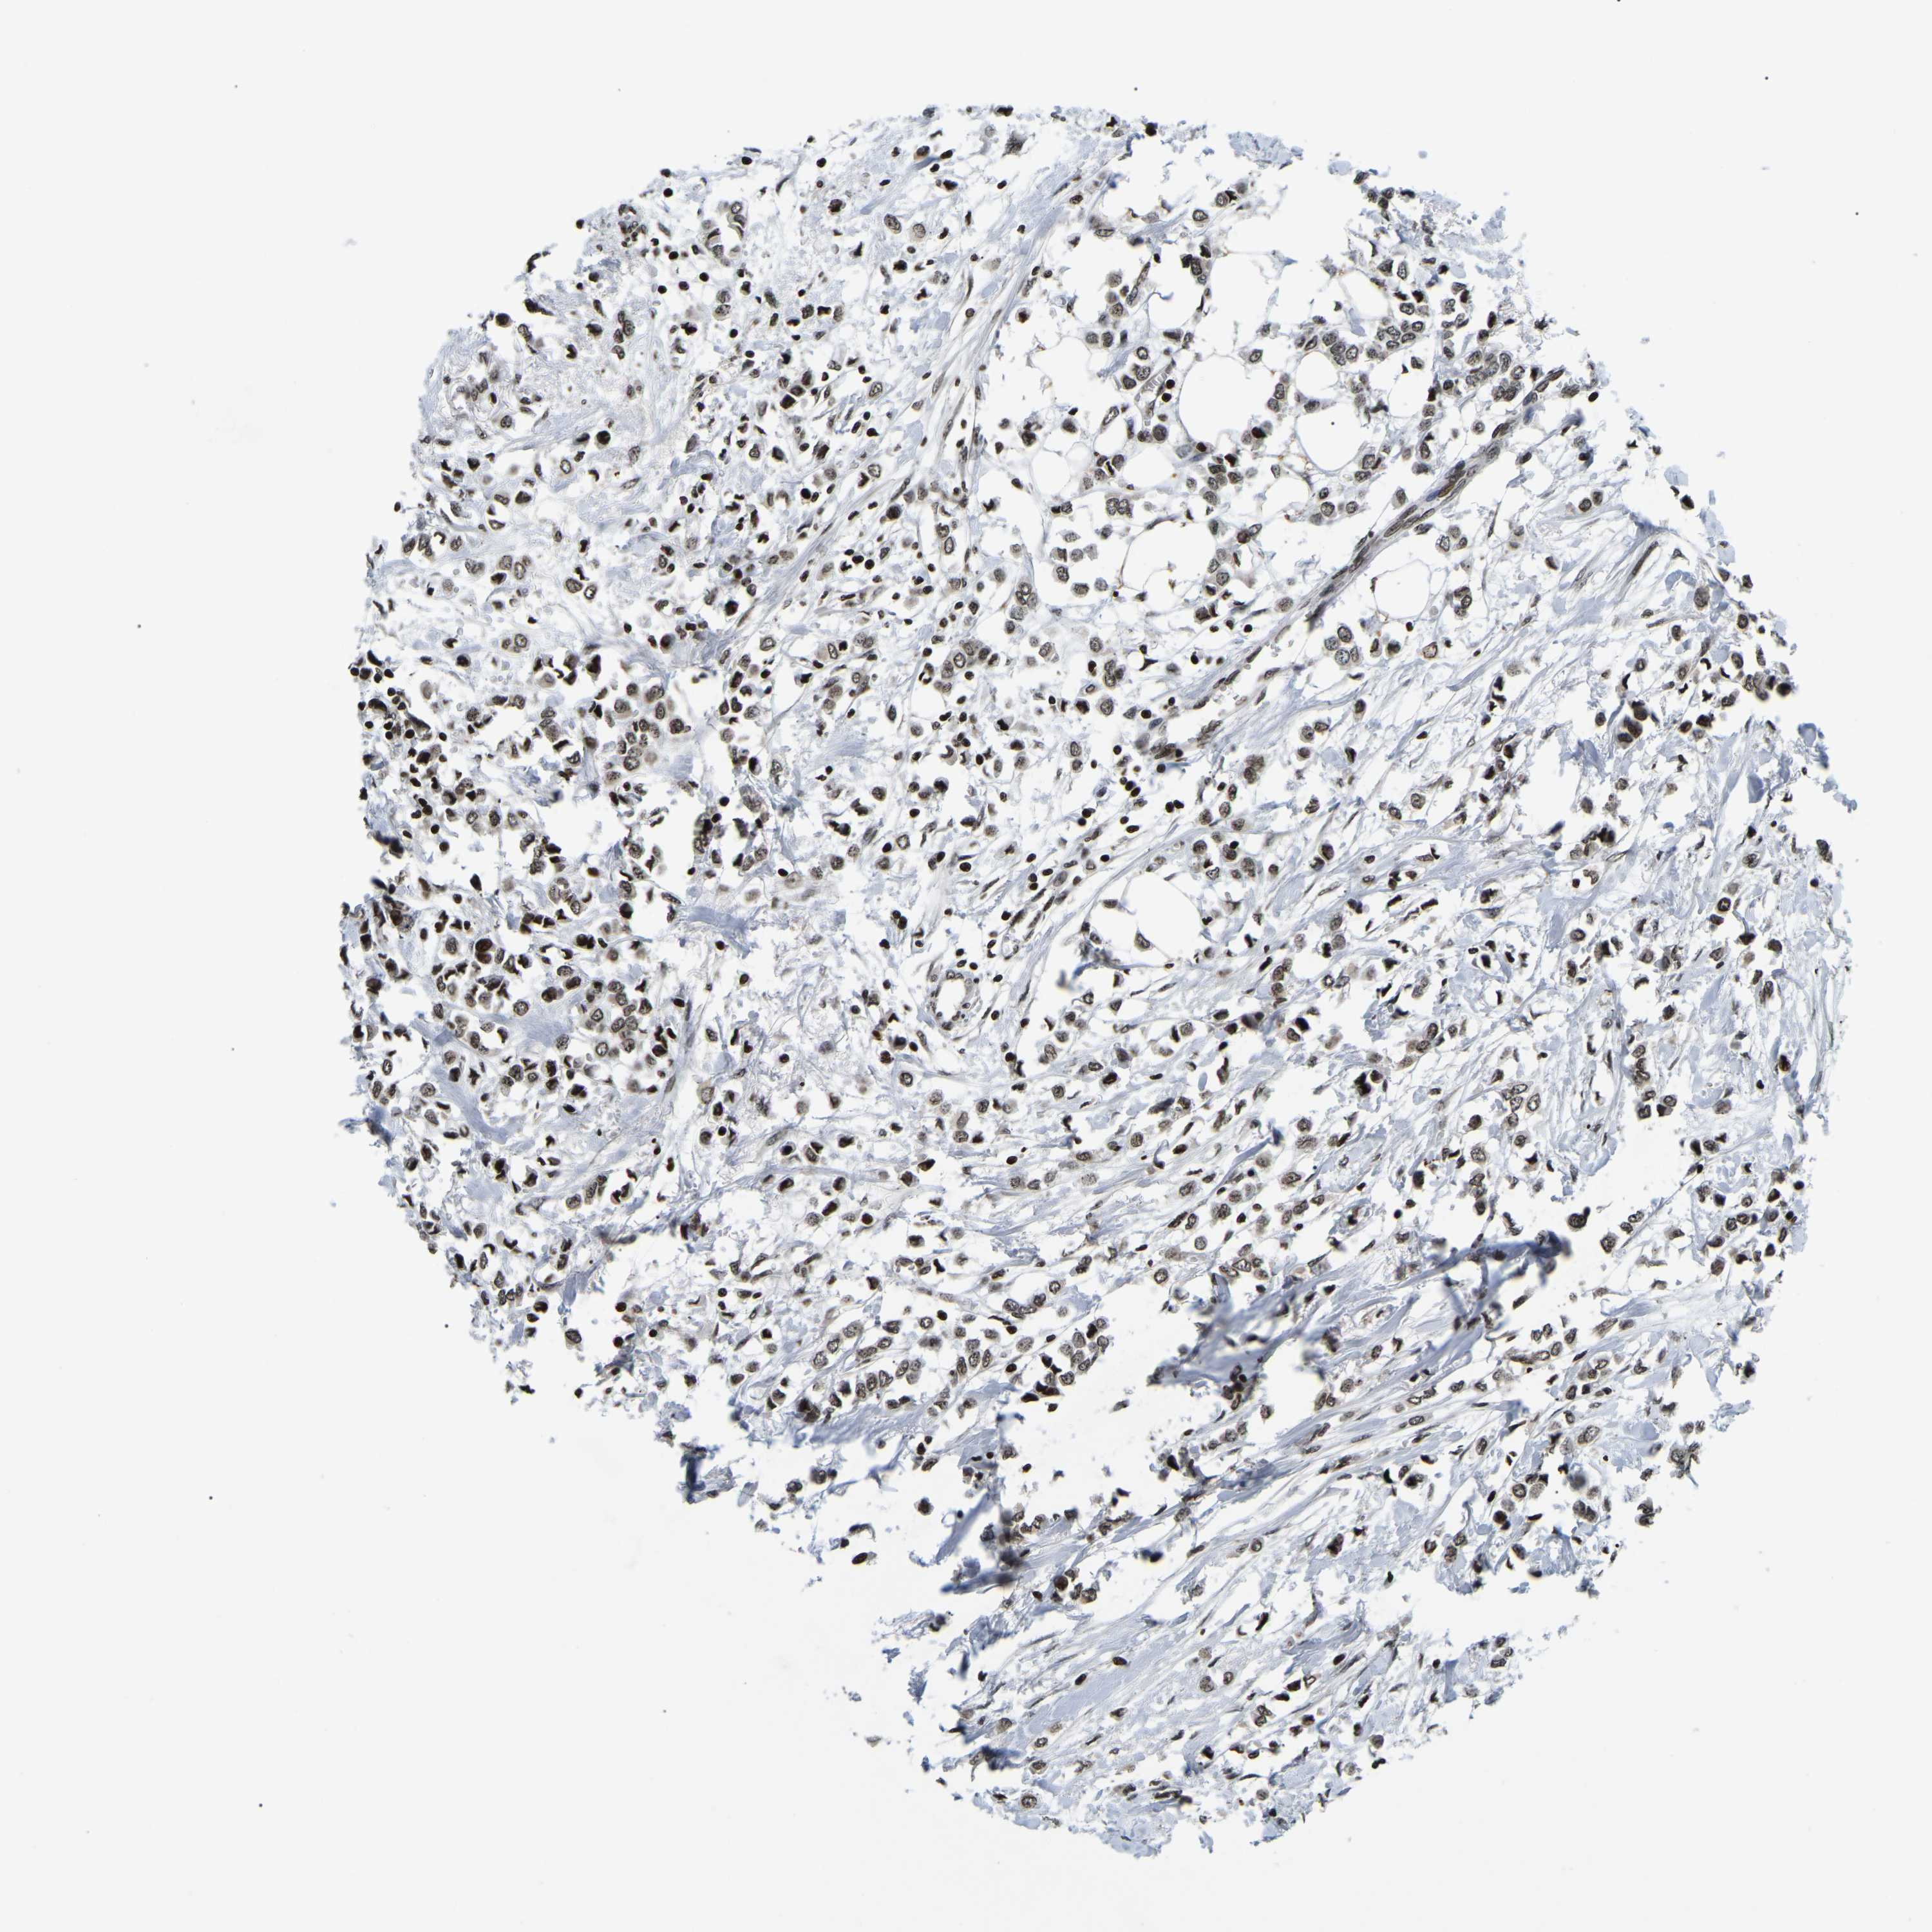

BRCA TCGA BRCA VALIDATION PROTEIN EXPRESSION